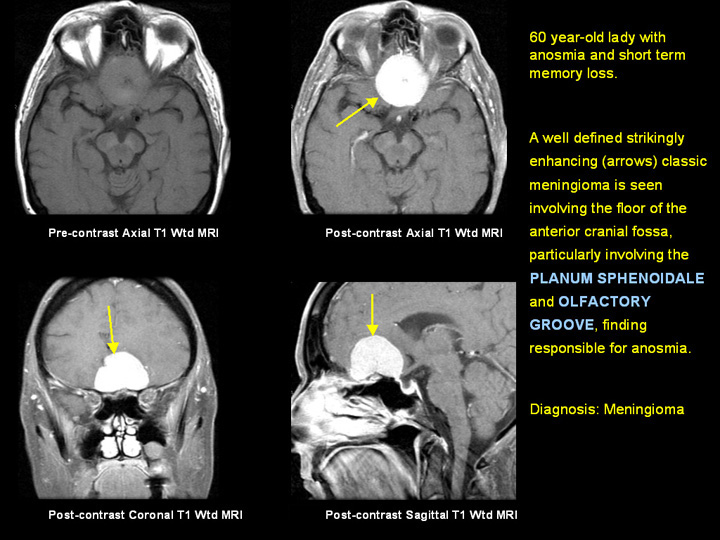

Case 1: CNS - Centers For Disease Control And Prevention

Case 1: CNS . History and Physical Examination . 9/17 MRI, brain and brain stem: There is a posterior left temporal ring-enhancing mass and significant MRI, olfactory groove meningioma arises in the midline; FORDS, p. 92 . Sequence Number- ... Retrieve Doc